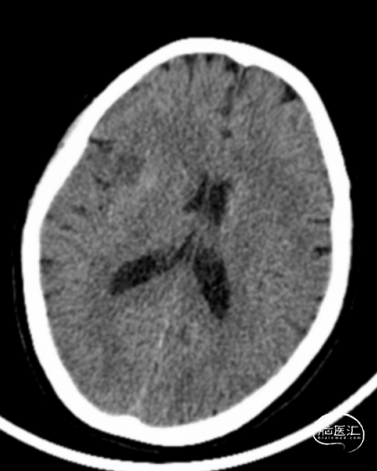

术前头颅CT示:颅内未见明显异常。

术后24小时头颅CT:右侧基底节区少量出血及低密度灶。